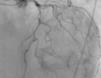

The patient was transferred to a center with hemodynamic laboratory for cardiac catheterization. On arrival, he was without pain and hemodynamically stable, but suffering from psychomotor agitation and spatial and temporal disorientation, in Killip class I; the ECG showed Q waves in the anteroinferior wall. Cardiac catheterization revealed three-vessel coronary disease, with subocclusive stenosis of the proximal segment of the left anterior descending artery (LAD) (culprit lesion), the proximal segment of the right coronary artery (RCA) (culprit lesion), and the distal segment of the circumflex artery (Cx). Angioplasty was performed with implantation of two Driver stents in the RCA and one in the LAD (Figures 4 and 5).